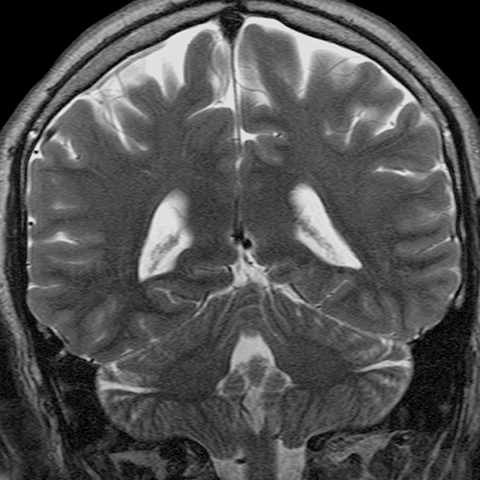

Cranial Meninges (normal) [5 of 8]